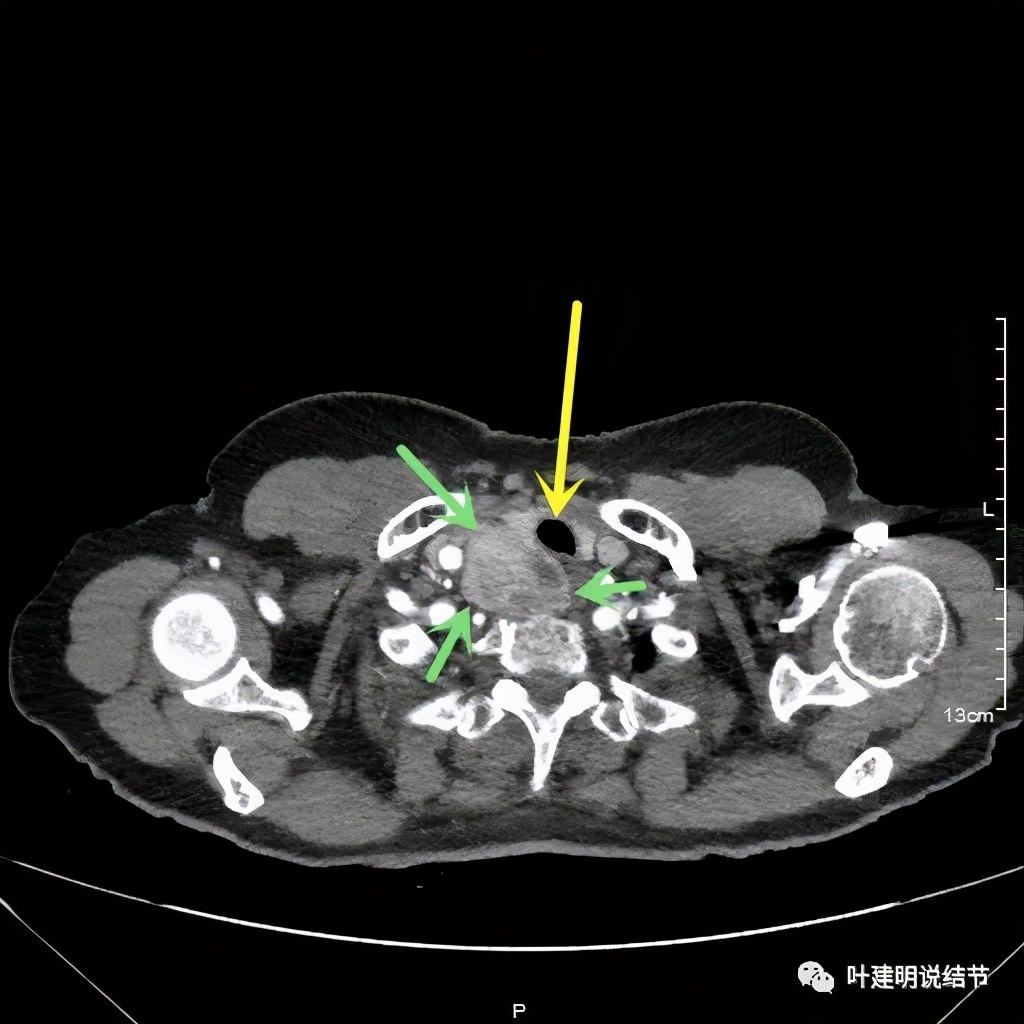

金华地区的某A,今年已经76岁了,近段时间觉得胸闷不适,还有刺激性咳嗽,总是不会好,到当地医院查了胸部CT,发现是纵隔肿瘤。当地医生建议她到金华市中心医院做下气管镜下穿刺活检,以明确肿瘤性质。因为认识我们医院的某外科主任,所以又建议她来找我,结果我一看她从当地带来的片子,是纵隔内巨大的占位,与气管关系密切,位于气管右侧、食管右前侧、上腔静脉左侧、无名静脉后侧,被诸多结构包绕着,而且肿瘤密度不均,靠气管与无名静脉侧间隙不清,首先考虑纵隔内恶性或交界性肿瘤,由于年纪这么大,手术风险较高,若与气管有侵犯,则手术达不到根治,我也觉得应该先行经气管镜下的穿刺活检,明确病理后再考虑怎么办。所以让某A住到呼吸内科去,打算行气管镜下纵隔肿瘤穿刺活检。因当地的片子扫到胸顶部为止,没有做增强,我们先取本院增强片子上达胸顶,下达肿瘤下缘的范围来看看肿瘤的样子:

胸顶就开始有肿瘤了,黄色示受压迫移位的气管,红色示肿瘤

上图红色示肿瘤,黄色示气管,粉色示肿瘤与气管关系密切,而且肿瘤密度不均杂乱